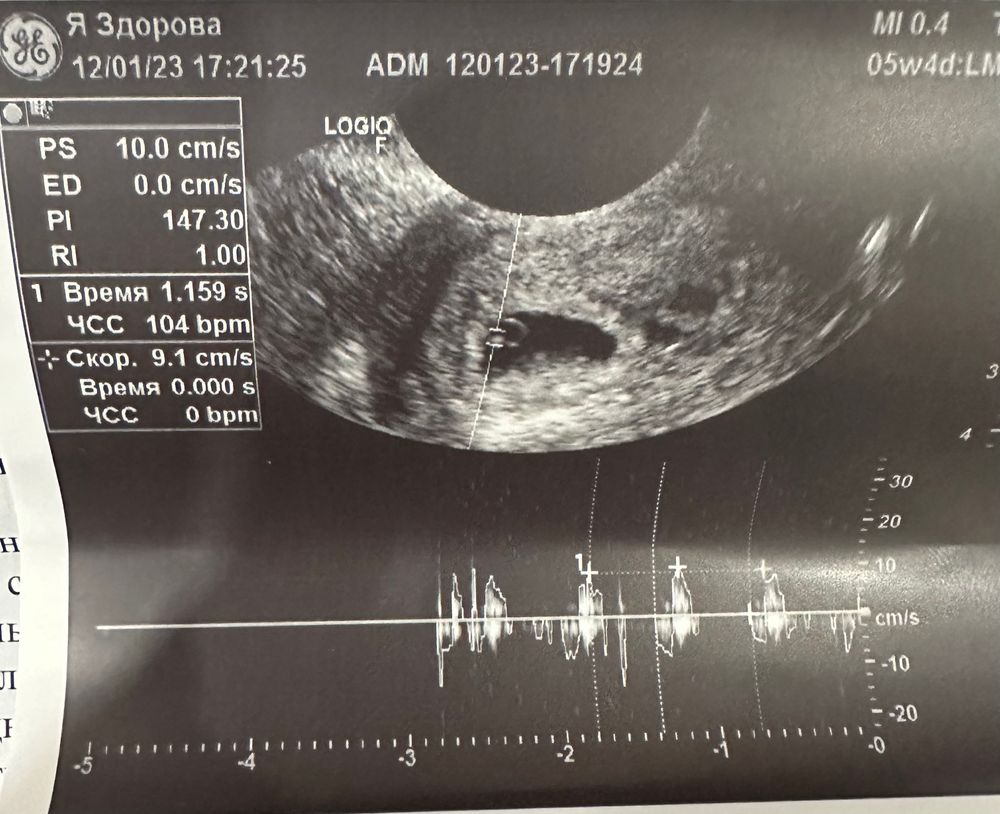

Наши 5нед+4 и СБ

вобщем в итоге всё хорошо, растем - по ПЯ и КТР даже на 1-2 дня быстрее, сердечком стучим, значит всё идет как нужно)